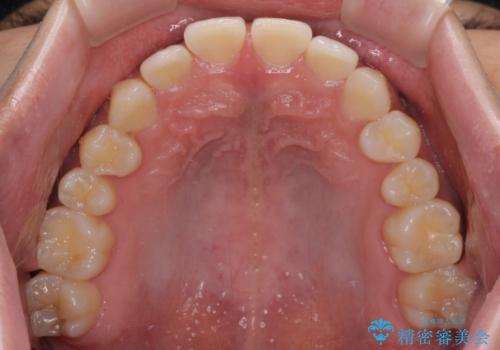

隙間の空いた前歯を治したい 上顎の部分矯正

- 上顎前歯の隙間を気にして来院された患者様です。

下顎前歯に叢生がありましたが、特に気にしていらっしゃいませんでした。

下顎臼歯にインプラント補綴治療がされており、全顎治療するにはクラウンの作り替えが必要となる旨を説明し、ワイヤー装置により上顎のみの矯正治療を行うこととしました。